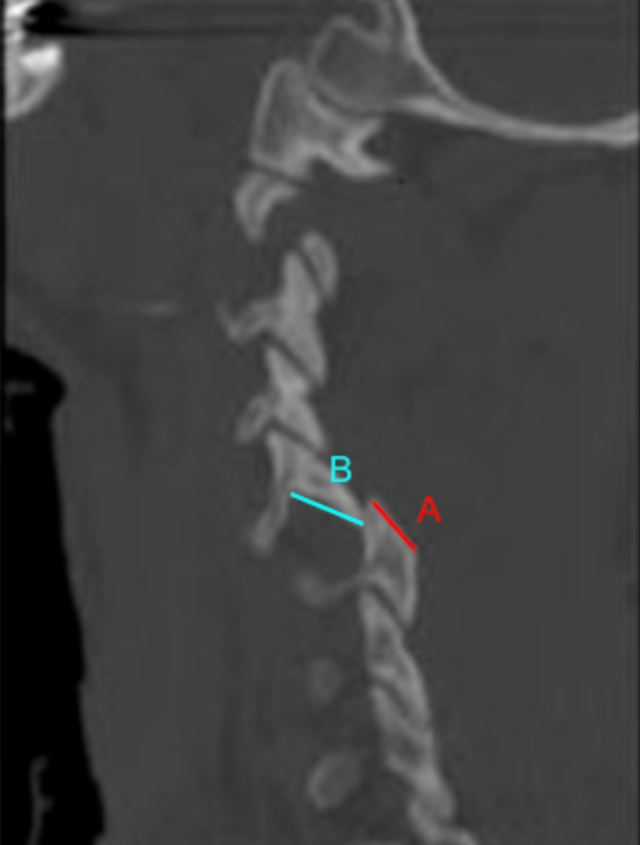

•  Measure Facet Length (A):

• Measure the total anteroposterior length of the superior articular facet of the inferior vertebra.

•  Measure Overlap Length (B):

• Measure the portion of the inferior articular facet that remains overlapped with the superior articular facet in the anteroposterior direction.

•  Calculate Percent Facet Overlap:

Facet Overlap (%) = (BA)100